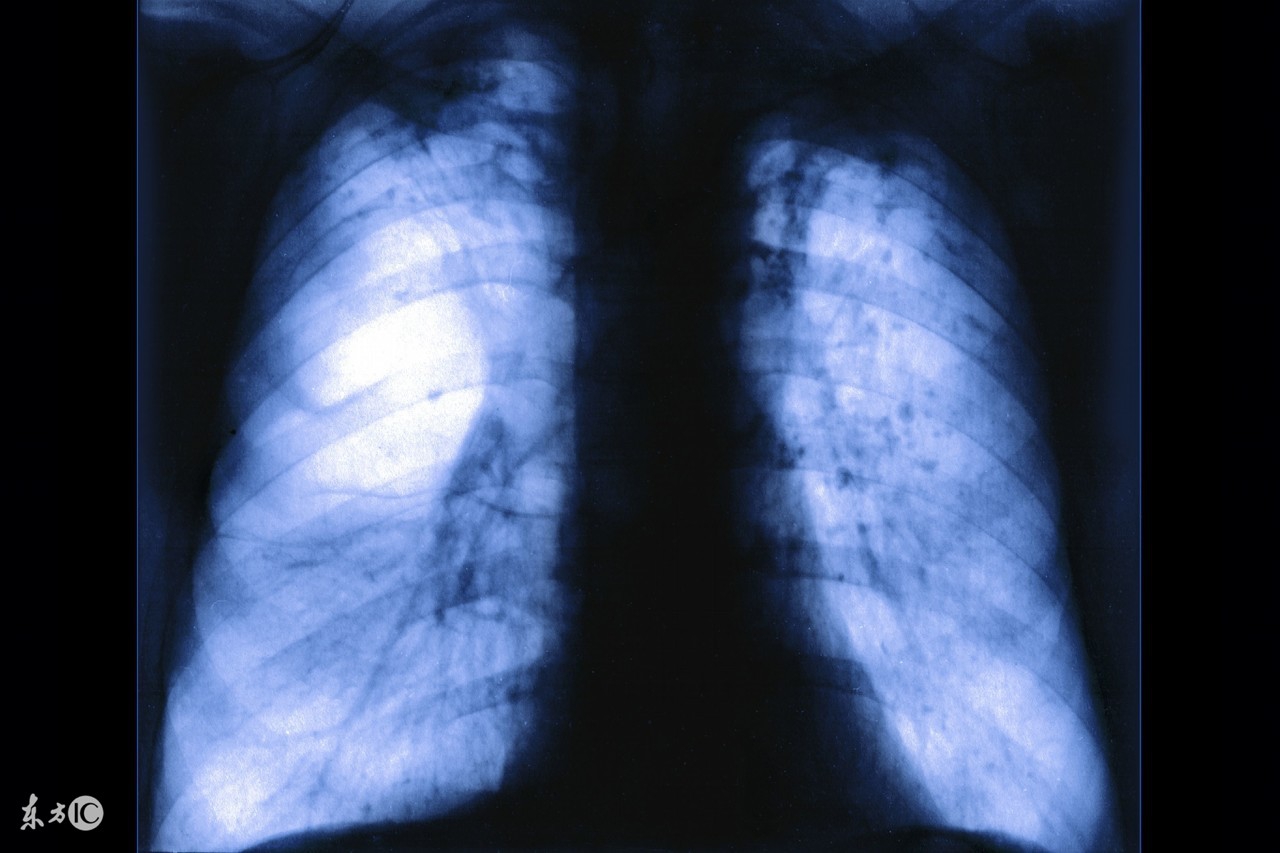

老年人肺气肿怎么治